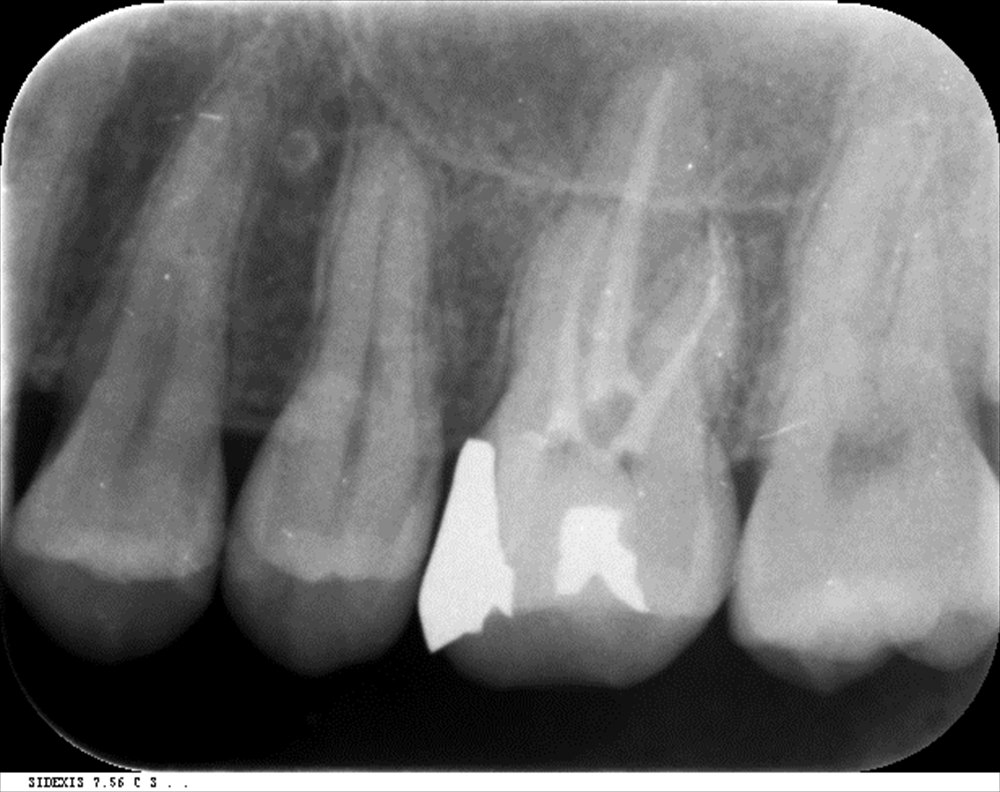

丁寧に

二回で根管充填

レントゲンでもOK症状なし!遠心は湾曲根管でしたがプロテーパーネクストが活躍!!